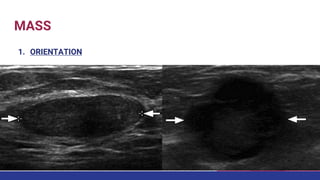

MASS

1. ORIENTATION

• #35 unique to US-imaging, and defined as parallel (benign) or not parallel (suspicious finding) to the skin.

• #59 MAMMOGRAM SHOWED A 1.5CM MASS AND USG WAS ADVICED WHICH SHOWED A PARELLEL SOILD WELL CIRCUMSCRIBED MASS THAT IS PROBABLY BENIGN